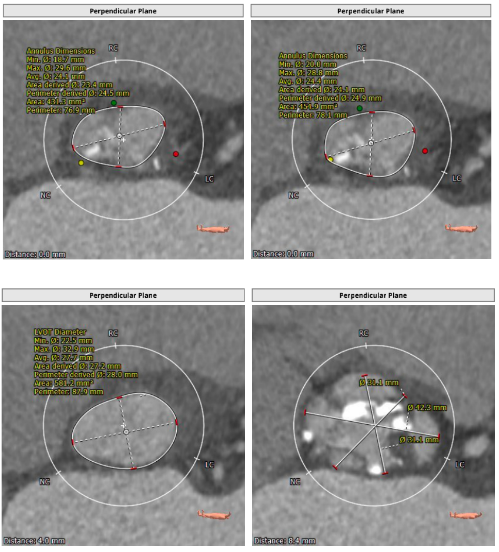

主动脉根部解剖: